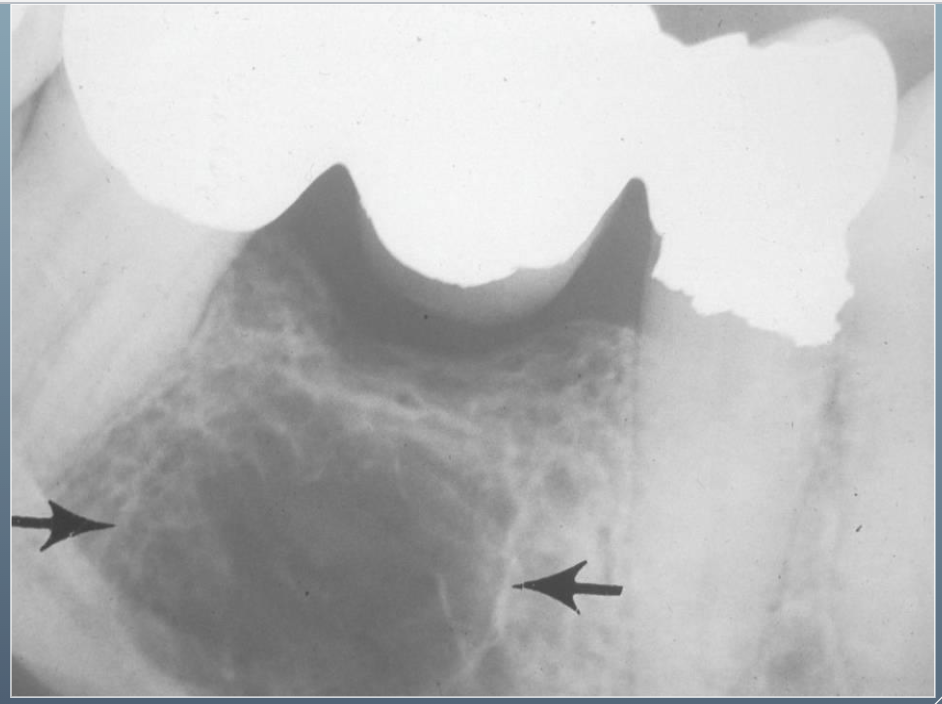

What’s this?

HEMATOPOIETIC BONE MARROW DEFECT

FOCAL OSTEOPOROTIC BONE MARROW DEFECT